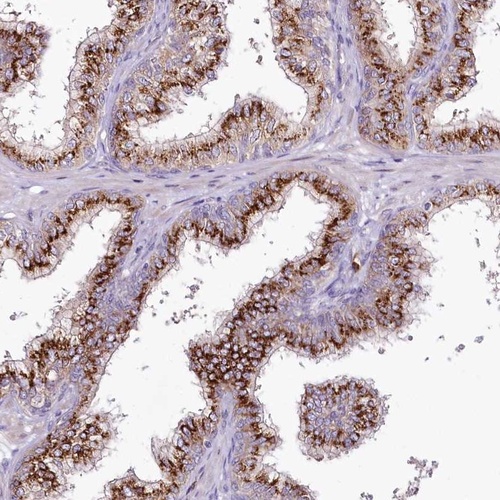

Immunohistochemical staining of human prostate shows strong granular cytoplasmic positivity in glandular cells.